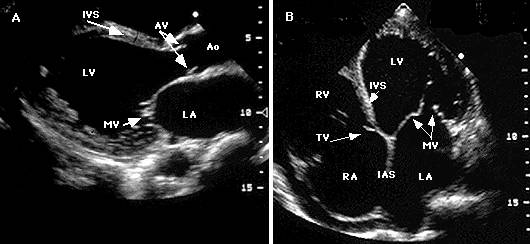

Ecocardiografia permite evaluarea afectarii functiei contractile, excluderea unor boli valvulare sau pericardice. Se apreciaza forma si functia VS (tipic VS globulos cu functie contractila global alterata), gradul insuficientelor valvulare, prezenta trombozei intracavitare (intraatriala sau intraventriculara). Cresterea dimensiunilor cavitatilor stangi si drepte este progresiva cu cresterea clasei functionale NYHA. Producerea emboliilor se asociaza cu dimensiunea VS si fractia de ejectie (FE).

Ecocardiografia

Confirma diagnosticul de CMH, cuantifica elementele morfologice - distributia hipertrofiei, functionale - hipercontractilitatea VS si hemodinamice - gradientul intraventricular.

Caracterele ecocardiografice sunt :